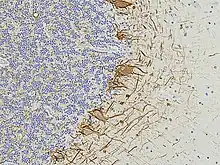

Neurofilament light polypeptide, also known as neurofilament light chain, abbreviated to NF-L or Nfl and with the HGNC name NEFL is a member of the intermediate filament protein family. This protein family consists of over 50 human proteins divided into 5 major classes, the Class I and II keratins, Class III vimentin, GFAP, desmin and the others, the Class IV neurofilaments and the Class V nuclear lamins. There are four major neurofilament subunits, NF-L, NF-M, NF-H and α-internexin. These form heteropolymers which assemble to produce 10nm neurofilaments which are only expressed in neurons where they are major structural proteins, particularly concentrated in large projection axons. Axons are particularly sensitive to mechanical and metabolic compromise and as a result axonal degeneration is a significant problem in many neurological disorders. The detection of neurofilament subunits in CSF and blood has therefore become widely used as a biomarker of ongoing axonal compromise. The NF-L protein is encoded by the NEFL gene.[5][6] Neurofilament light chain is a biomarker that can be measured with immunoassays in cerebrospinal fluid and plasma and reflects axonal damage in a wide variety of neurological disorders.[7][8] It is a useful marker for disease monitoring in amyotrophic lateral sclerosis,[9] multiple sclerosis,[10] Alzheimer's disease,[11][12] and more recently Huntington's disease.[13] It is also promising marker for follow-up of patients with brain tumors.[14] Higher levels of blood or CSF NF-L have been associated with increased mortality, as would be expected as release of this protein reflects ongoing axonal loss.[15] Recent work performed as a collaboration between EnCor Biotechnology Inc. and the University of Florida showed that the NF-L antibodies employed in the most widely used NF-L assays are specific for cleaved forms of NF-L generated by proteolysis induced by cell death.[16] Methods used in different studies for NfL measurement are sandwich enzyme-linked immunosorbent assay (ELISA), electrochemiluminescence, and high-sensitive single molecule array (SIMOA).[17]

- Shaw G, Madorsky I, Li Y, Wang Y, Rana S, Jorgensen M, et al. (April 2023). "Uman Type Neurofilament Light Antibodies Are Effective Reagents for the Imaging of Neurodegeneration". Brain Communications. 5 (2): fcad067. doi:10.1093/braincomms/fcad067. PMC 10120172. PMID 37091583.